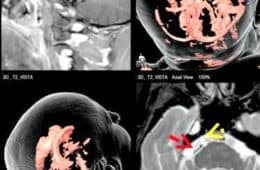

La Cirugía en el tratamiento de la Neuralgia Esencial del Trigémino. Parte 3 Veíamos en dos artículos anteriores que la Neuralgia Esencial del Trigémino es el trastorno más doloroso conocido en Medicina y representa el 1,5% de todas las consultas en Neurología y un alto porcentaje en las Unidades del Dolor. De origen desconocido, la … Sigue leyendo La Cirugía en el tratamiento de la Neuralgia Esencial del Trigémino. Parte 3